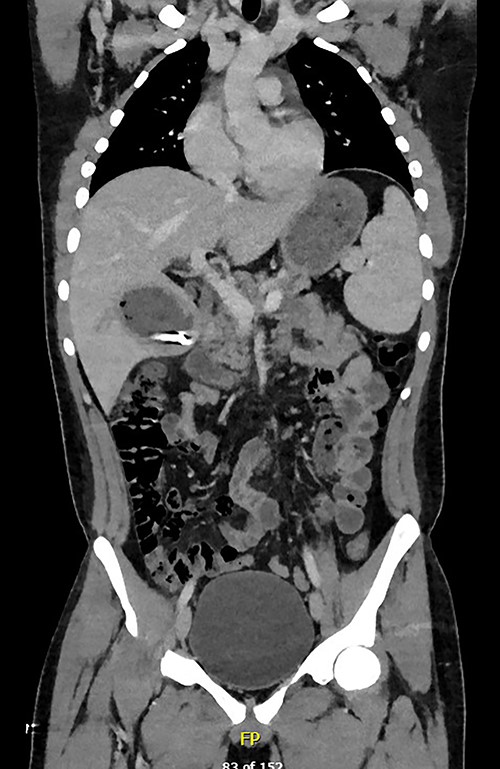

A full lab panel was ordered and revealed a total bilirubin of 1.1, direct bilirubin 0.5, lactate dehydrogenase 196, alkaline phosphatase 80, aspartate transaminase 46 and alanine transaminase 58. A computed tomography (CT) angiographic scan of the chest, abdomen and pelvis revealed the presence of a rim enhancing fluid collection in hepatic segment V with internal gas and containing a metallic foreign body, measuring 8 × 5 cm and consistent with abscess formation (Figs 2–4). The linear tract of the bullet in the right iliac crest was visualized in the CT as well.

Transverse plane of the CT showing the hepatic collection measuring 8 × 5 cm.

Transverse plan of the CT showed the bullet lodged in segment 5 of the liver.

Coronal plane of CT showing the retained bullet and hepatic abscess.